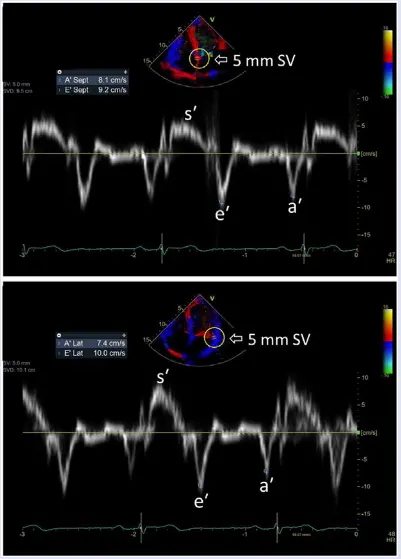

Mitral annular velocity: e’ velocity (cm/s): peak early diastolic modal velocity after ECG T-wave

Mitral annular velocity: a’ velocity (cm/s): peak late diastolic modal velocity after ECG P-wave

As a general rule of thumb, normal LV relaxation is suggested by medial e’ ≥ 9 cm/s and lateral e’ ≥ 12 cm/s. However, values can vary by age 👇

- According to Dr. Oh, e’ velocity is money 💵 because normal LV relaxation (e’) means you must have normal diastolic function. This is reflected in the Step 1→Step 2 algorithm (Figure 2) proposed in the 2025 guideline update.4

- In other words, you can stop looking for other markers of diastolic dysfunction if you have normal e’ velocities.

- “Once you see that e’ is normal, you don’t need to look at anything else because you cannot have diastolic dysfunction with normal e’ velocities” - Dr. Oh

- “Normal e′ velocity is unusual in patients with diastolic dysfunction related to a myocardial abnormality or disease, which is a main reason that the joint Diastology Working Group recommends that an evaluation of diastolic function begins with e′ in patients with normal LV ejection fraction.” 3

Mitral inflow pattern in a ~30 yo patient with severe LVH who initially presented with HTN emergency.

If you just base it off the patient having medial e’ >6, lateral e’ >7, or average >6.5, then you may conclude that she has normal diastolic function. However, I’d argue that this would be incorrect. The patient is a ~30 yo with severe LVH. Bearing in mind her young age, you should expect her e’ velocities to be much higher if she truly had normal diastology. With her very high E/A ratio, she has Grade 3 DD.